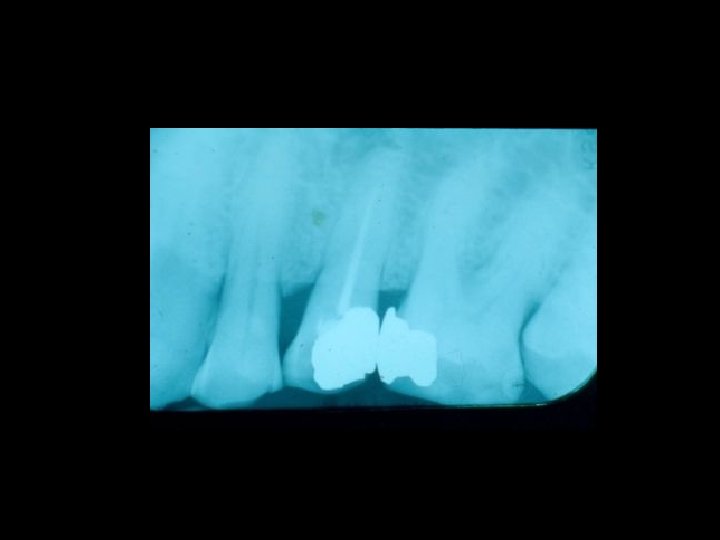

Responsabilità Ø Restauro della corona del dente Ø Trattamenti radicolari